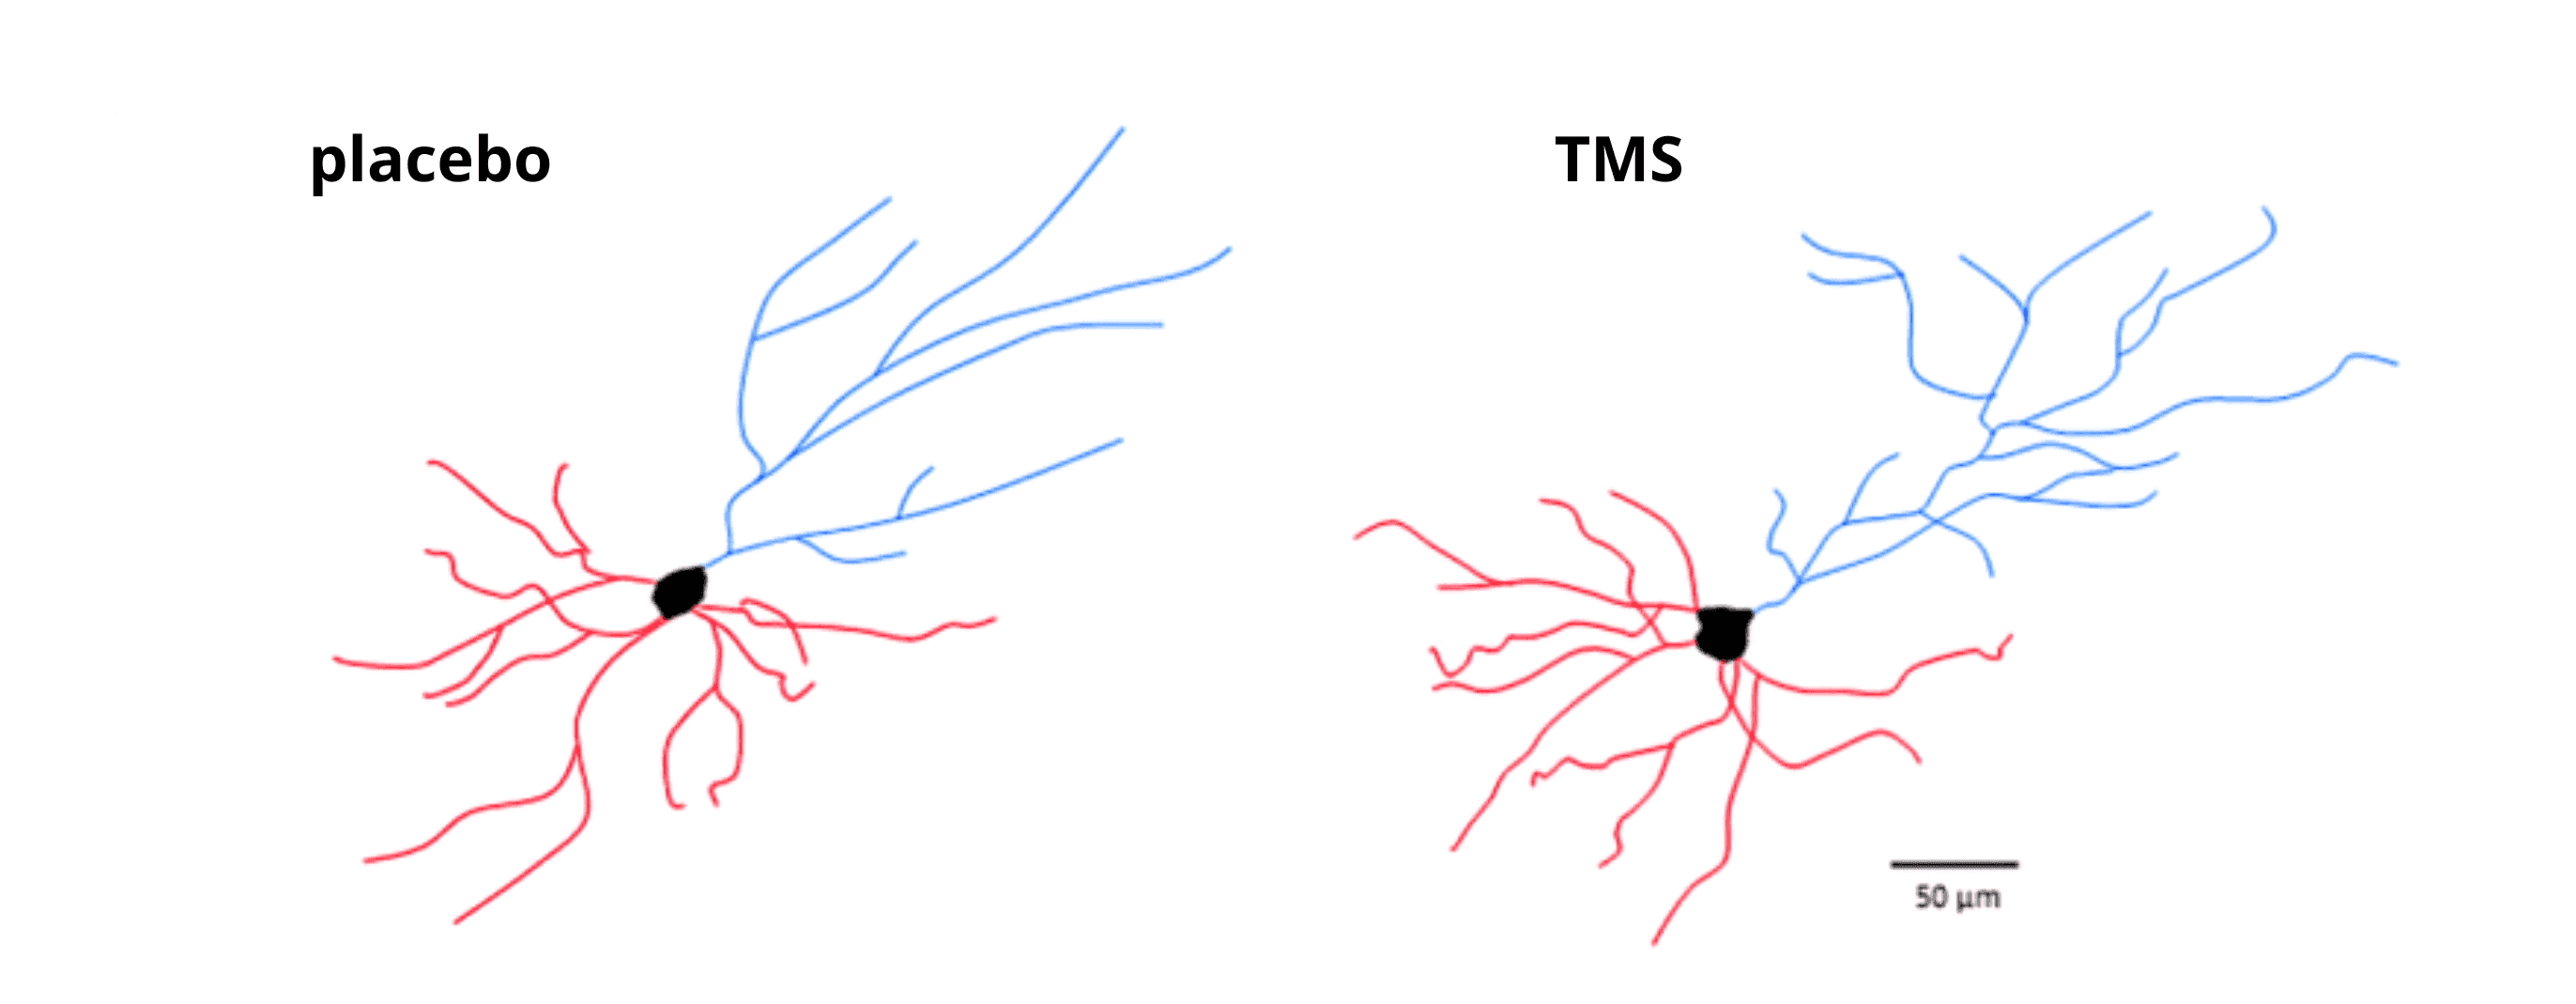

- Improved cognitive functioning

Some patients report better concentration, improved mood, and better sleep quality.